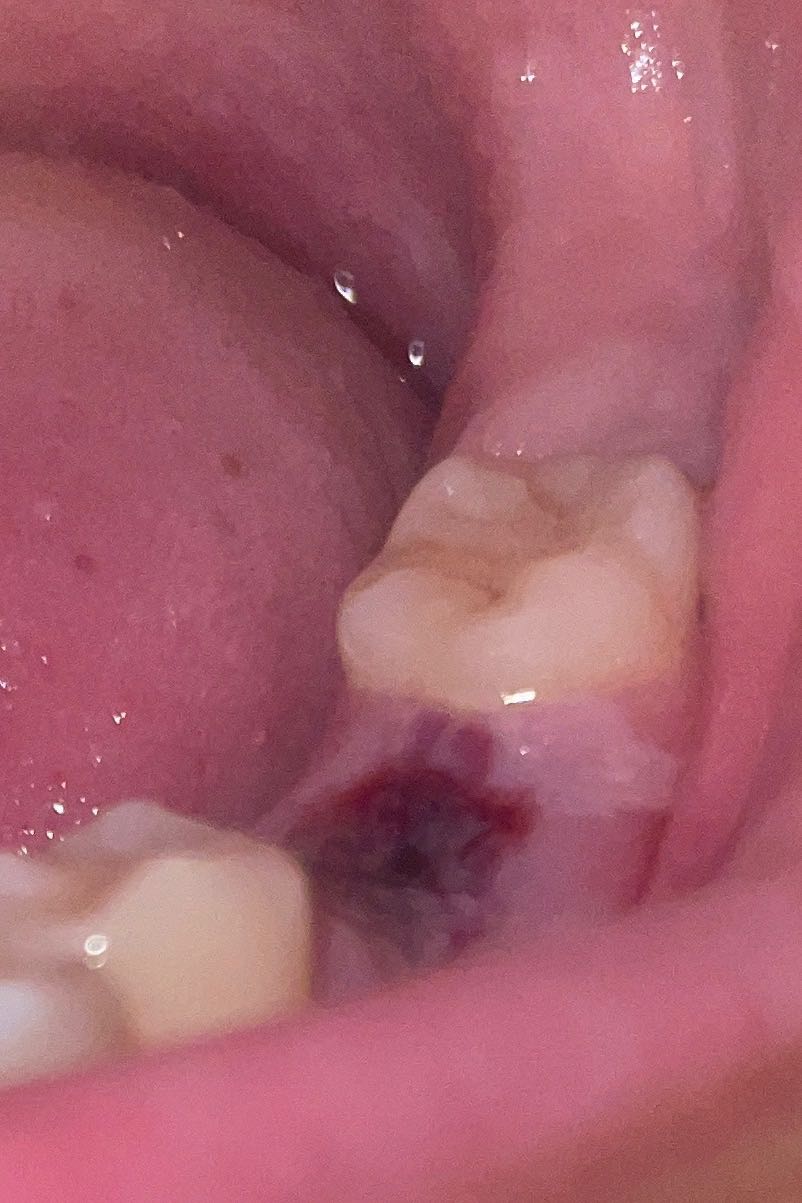

ไปถอนฟันมาเมื่อวานมีปวดที่เหงือกอันนี้ปกติใช่มั้ยคะ

รูปแผลลฟันค่ะ